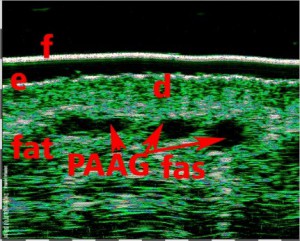

-Έγχυση Πληρωτικών Υλικών (Fillers)